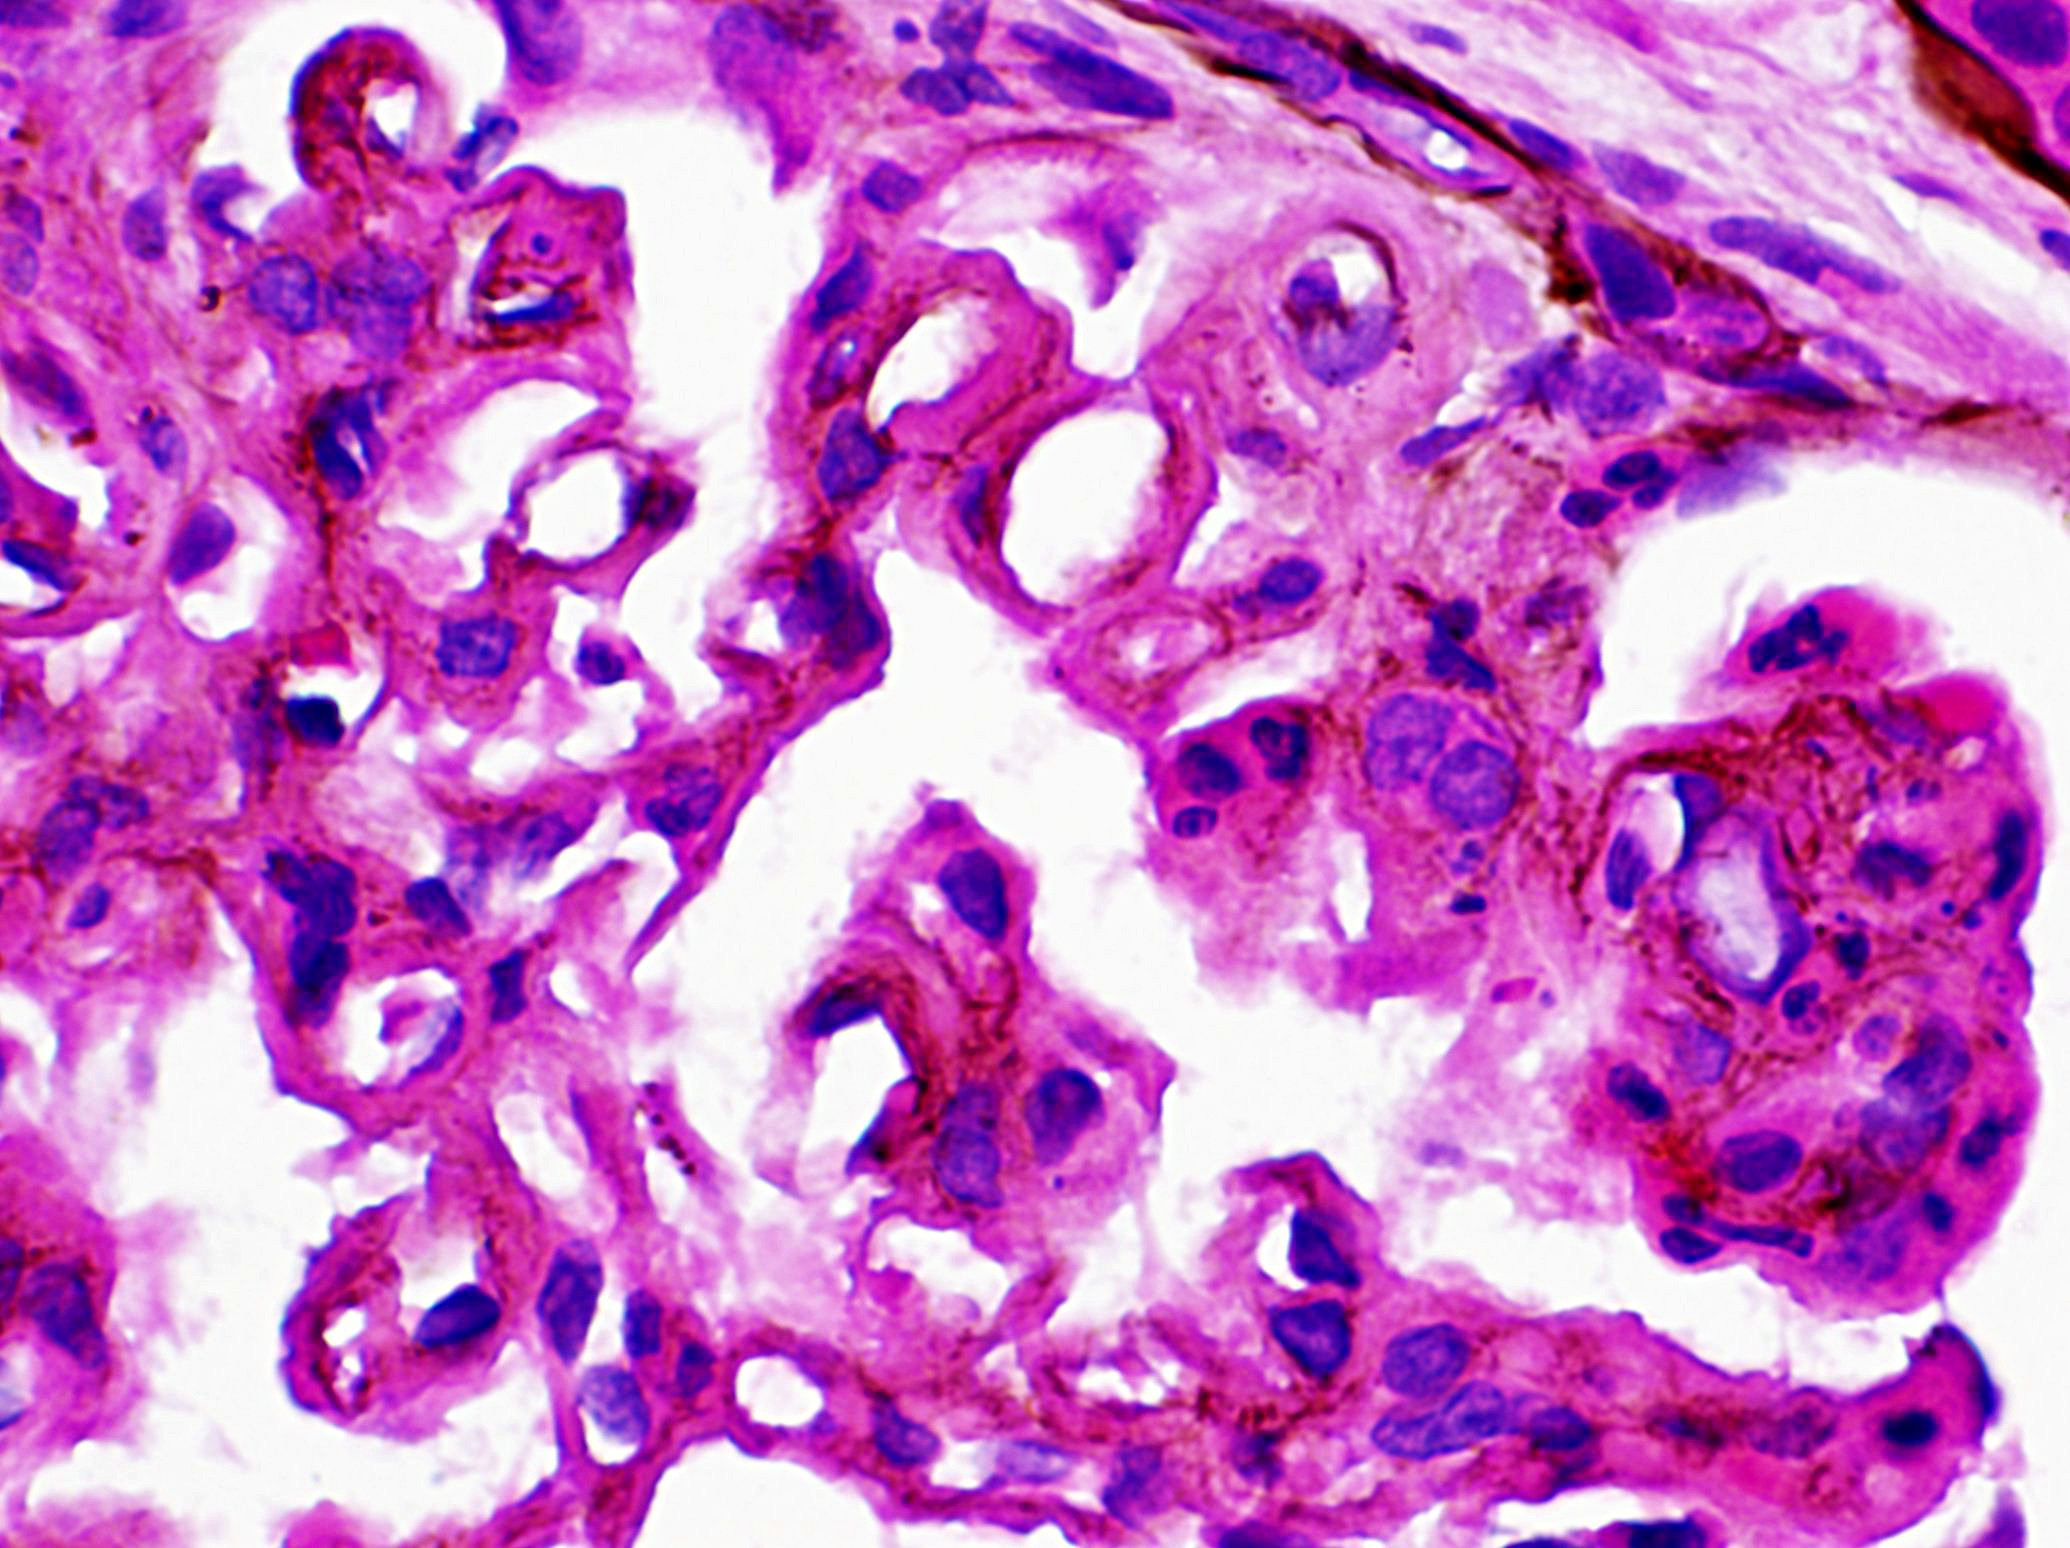

DDD, previously known as membranoproliferative glomerulonephritis (MPGN) type II, is now considered a subtype of C3 glomerulopathy, as MPGN pattern of glomerular injury, characterized by diffuse splitting of the glomerular basement membranes and mesangial hypercellularity with or without endocapillary hypercellularity (Fig A & B), is identified only in one third of the patients with DDD and is therefore misleading. The defining feature of DDD is ultrastructural finding of continuous, ribbon like, predominantly intramembranous, segmental subendothelial and mesangial globular intensely electron-dense deposits (fig: 4), from where the disease derives its name. These deposits show strong staining for C3 with absent or minimal staining for immunoglobulins and C1q, by immunofluorescence (Fig: 3).